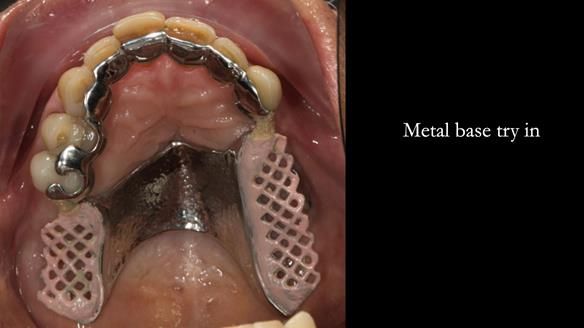

The upper jaw

In the upper arch:

- a failing upper left tooth supporting a bridge was removed

- an implant-supported bridge on the upper right was dismantled

A metal-based upper RPD was made,

with metal backings incorporated to future-proof the design

should further teeth fail.